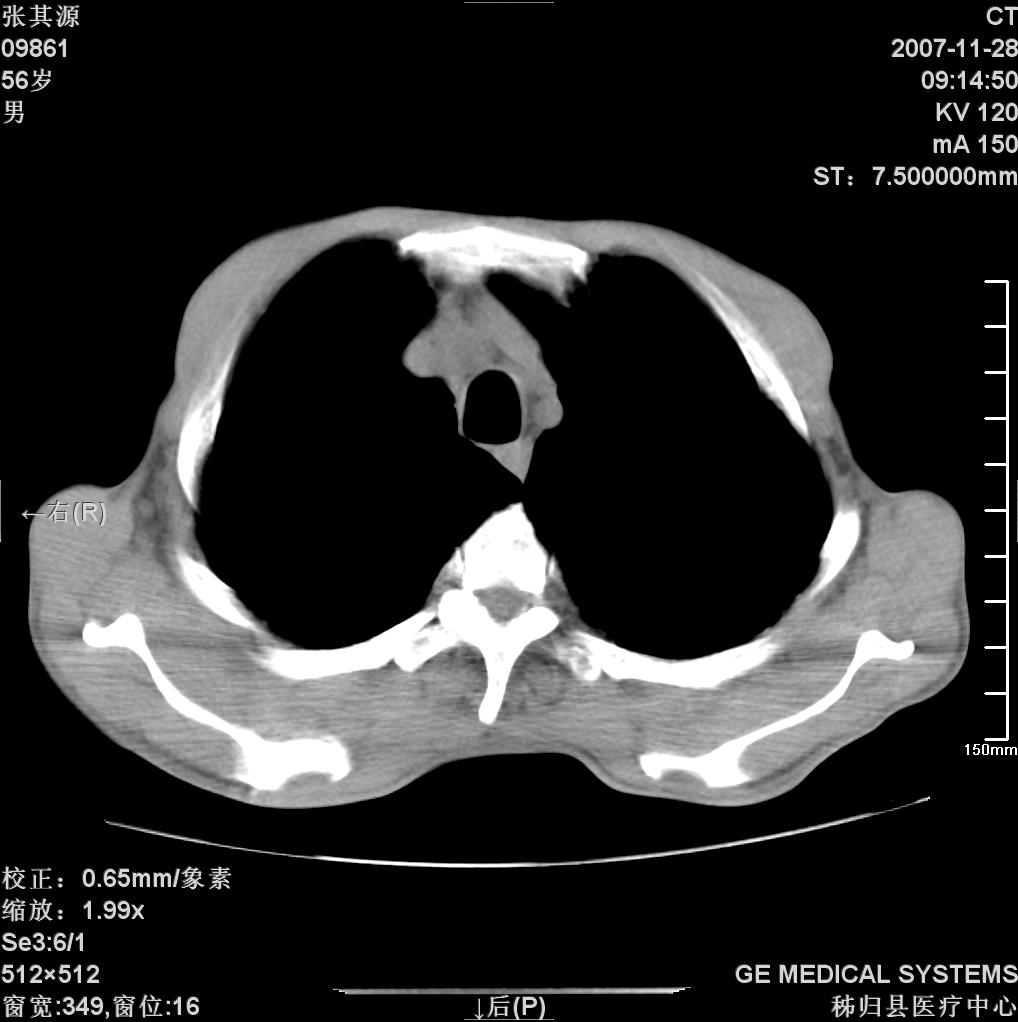

考虑tb不排除转移,(隆突处有肿大淋巴结,不好说是结核还是转移引起的)

双肺多发粟粒样病灶,右肺胸膜下结节样病灶,气管前腔静脉后及隆突下均见肿大淋巴结,结合胆道肿瘤病史首先考虑转移。另外心影密度略低,时间格显示,是否有贫血?查明白再手术吧!